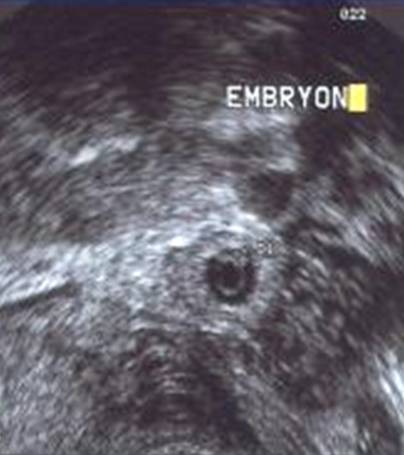

Aspect échographique d'une grossesse évolutive de 7 SA